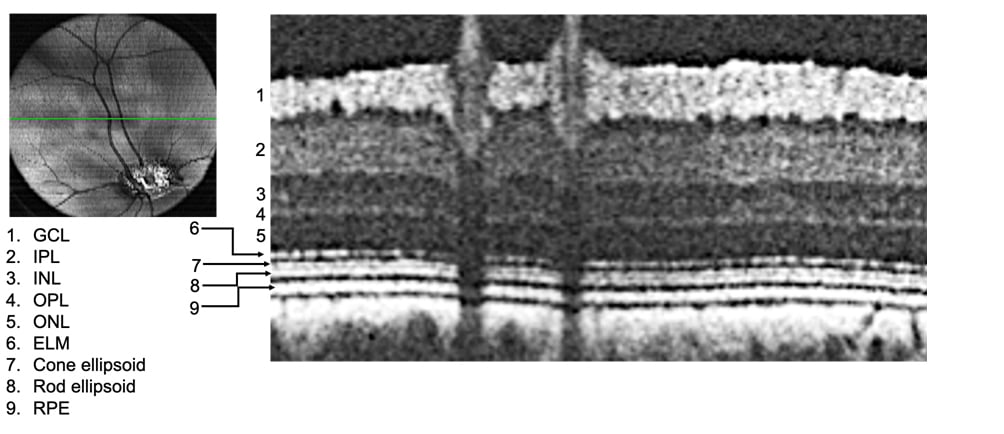

The pig retina has a very similar retinal architecture to that of a human retina. “Our funded research represents the mission of the Advanced Ocular Therapeutics Program of the Department of Ophthalmology & Visual Sciences at UMMS to carry out cutting-edge research to understand and design treatments for devastating blinding disorders. The collaborative environment and complimentary expertise of the UMMS faculty is best suited to accomplish these studies,” said Dr. Shlomit Schaal, Chair, Department of Ophthalmology & Visual Sciences, UMass Chan Medical School.

Figure:

Left: A Fundus image of a pig eye showing the retina and blood vessels. Right: A cross section of the region of the fundus denoted by the green line shows the different retinal layers. GCL: ganglion cell layer; IPL: inner plexiform layer; INL: inner nuclear layer; OPL: outer plexiform layer; ONL: outer nuclear layer; ELM: external limiting membrane; RPE: retinal pigmented epithelium. The layered architecture is similar to that of a human retina. (Imaged by Dr. Bhubanananda Sahu, Research Specialist, Department of Ophthalmology & Visual Sciences, UMMS).